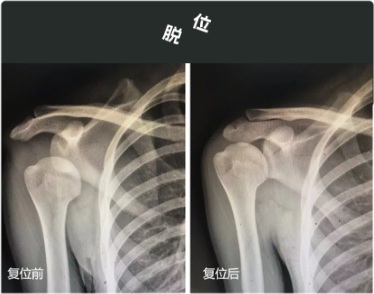

一扯胳膊

搞不好就关节脱位了